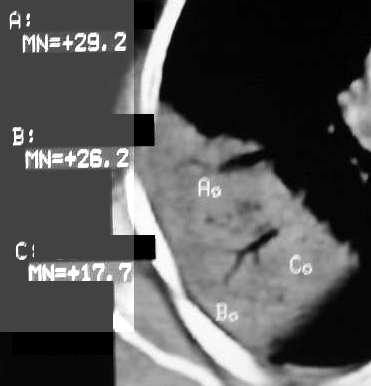

右肺上叶尖后段大片扇形实变影,密度较均匀,内见支气管空气造影征,气管腔静脉间淋巴结稍大呈小结节影,结合临床考虑大叶性肺炎。

右肺上叶肺实变,内见①支气管气像②边缘模糊③叶间裂稍饱满这些都是支持肺炎的证据。尤其是边缘模糊,其病理学依据是炎症渗出性物质通过肺泡间孔和/或呼吸性细支气管向临近的肺组织蔓延渗透,和其他表现在一起成为诊断肺炎的重要表现。

右肺上叶尖后段大片扇形实变影,密度较均匀,内见支气管空气造影征,气管腔静脉间淋巴结稍大呈小结节影,结合临床考虑大叶性肺炎

右肺上叶尖后段大片扇形实变影,密度较均匀,内见支气管空气造影征,气管腔静脉间淋巴结稍大呈小结节影,结合临床考虑大叶性肺炎。建议抗炎治疗后复查.